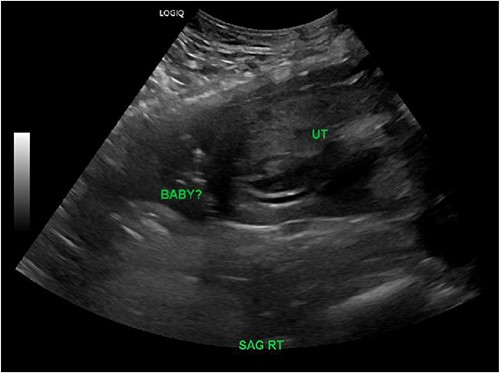

The patient’s initial hemoglobin was 12.2 g/dL, and her platelet count was 297 k/uL. A Focused Assessment with Sonography in Trauma (FAST) exam was performed and negative. No fetal architecture was noted within the uterine cavity during the FAST exam. Computerized tomography scan of the abdomen and pelvis showed a gravid uterus with mild scattered intraperitoneal free fluid and scattered increased density greatest ventral to the uterus, suggesting a hemoperitoneum with possible associated uterine rupture. Transvaginal ultrasound revealed no evidence of an intrauterine gestation and free fluid was noted within the cul-de-sac (Fig. 1). Given the high suspicion of uterine rupture based on the clinical presentation and imaging, an exploratory laparotomy was performed.

Right sagittal view on transvaginal ultrasound showing an empty uterine cavity with possible fetus outside of the uterus.